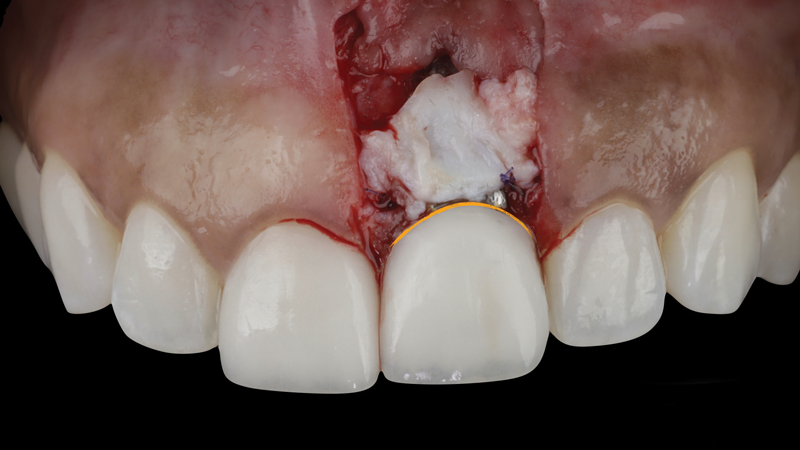

The patient in this case had undergone implant therapy at the site of tooth No. 9 and was restored with a cement-retained restoration more than 5 years prior. At presentation, the site demonstrated a peri-implant soft-tissue dehiscence that extended approximately 3-mm apical to the gingival margin of tooth No. 8. Thin and erythematous marginal tissue was evident at the zenith (Figure 2). The crown was removed, and a partial thickness flap was reflected using a papilla-sparing incision design. This revealed that the implant was positioned too far facially and that its body was visible through a very thin layer of bone (Figure 3 and Figure 4). The first objective of treatment was to minimize the facial extent of the emerging abutment and crown. To accomplish this, the facially positioned abutment and implant crown margin were both recontoured. The second treatment objective was to provide additional supracrestal soft tissue that would more adequately maintain the peri-implant margin. The tuberosity was selected as a donor site due to its dense, high-quality connective tissue, low propensity for shrinkage, and association with minimal patient discomfort. Once the graft was secured (Figure 5 through Figure 7), the flap was coronally positioned (Figure 8). After a healing period of 2 weeks, the margin of tooth No. 9 exhibited an ideal position in relation to its contralateral counterpart and demonstrated increased soft tissue thickness (Figure 9). Three months postoperatively, further healing had improved the esthetics and the position of the margin had been maintained (Figure 10).

(5.) After the abutment and crown were recontoured, a soft-tissue graft was taken from the patient’s tuberosity and secured over the implant to add supracrestal volume, and the restoration was replaced. Note the planned position of the margin indicated in orange.

Figure 5

(6.) After the abutment and crown were recontoured, a soft-tissue graft was taken from the patient’s tuberosity and secured over the implant to add supracrestal volume, and the restoration was replaced. Note the planned position of the margin indicated in orange.

Figure 6

(7.) After the abutment and crown were recontoured, a soft-tissue graft was taken from the patient’s tuberosity and secured over the implant to add supracrestal volume, and the restoration was replaced. Note the planned position of the margin indicated in orange.

Figure 7